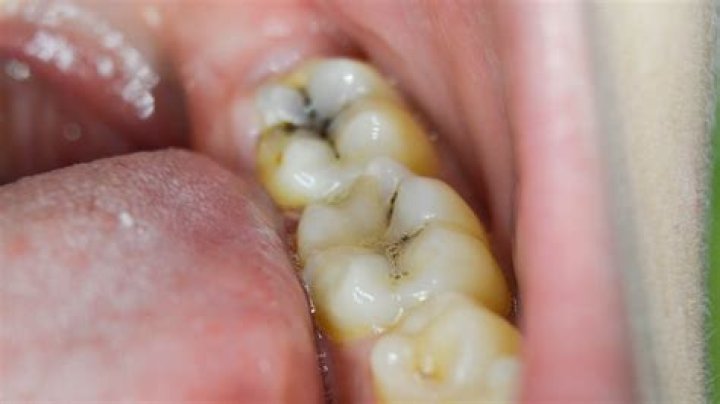

Often a cavity will look like a dark spot on the tooth, typically yellow, brown, or black in color. Early on, it may resemble tooth staining or a slight discoloration. As cavities progress, the holes get bigger and usually darker.

A black spot on the tooth can develop into a monster

Cavities vary greatly in appearance. In general, however, they appear as small holes, chips or dark spots on teeth. The holes can be as small as dots or as large as the entire tooth. Sometimes they look brown, yellow or black.

What does early stage cavity look like?

Does a black spot on tooth mean cavity?

Cavity, or tooth decay: Perhaps the most common cause for a black spot on your molar teeth is tooth decay, or a cavity. A cavity forms when the build-up of plaque, which contains acids, is allowed to erode the surface enamel of a tooth. A hole in the tooth's protective layer sometimes shows as a black dot.